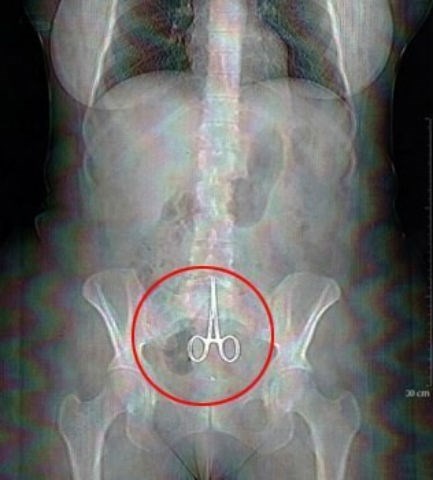

| Cô Nicole Haynes đã qua đời bất ngờ sau ca phẫu thuật nội soi ổ bụng đơn giản. Sau đó nhân viên bệnh viện đã phát hiện một đoạn phim ghi lại toàn bộ quá trình phẫu thuật. Nội dung đoạn phim cho thấy, các bác sĩ chịu trách nhiệm về ca mổ đã bỏ quên… kéo trong bụng bệnh nhân và không thực hiện đầy đủ những thao tác cần thiết khi hoàn thành phẫu thuật. |